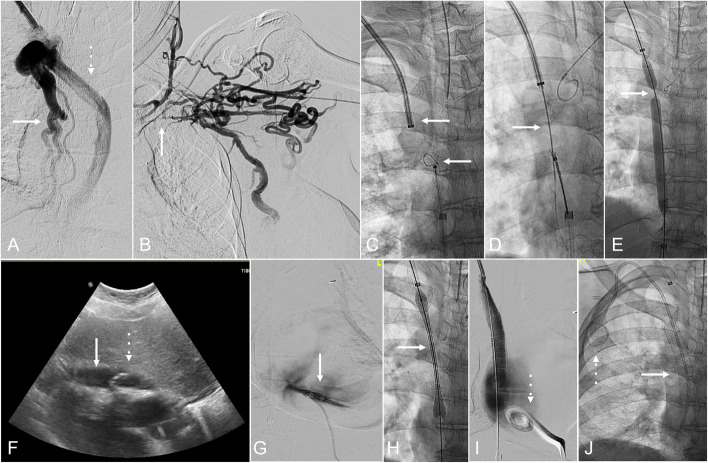

Materials and methods: An institutional protocol was established for intraprocedural transthoracic echocardiographic monitoring during the TCVO recanalization procedures. The lower chest and upper abdomen were prepared within the sterile field. A separate stand was set up with unopened supplies needed for pericardial drain placement. Intermittent echocardiographic monitoring was performed throughout the TCVO procedure using a dedicated curvilinear probe prepared on the field. If indicated, an image guided pericardial drain was placed expeditiously.

Results: Four cases of cardiac tamponade were encountered during or immediately post-procedure. All cases demonstrated technically successful and prompt pericardial drain placement with immediate reversal of the tamponade physiology.